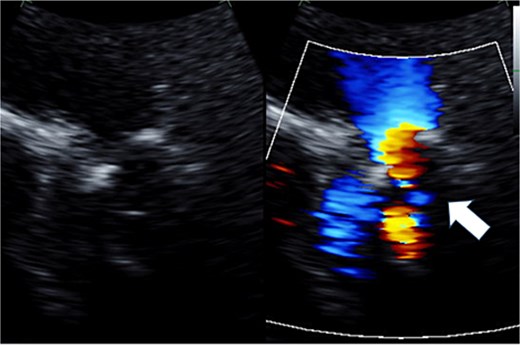

The patient was a 50-year-old female with pulmonary (PV) and tricuspid valve (TV) regurgitation. At 8 years old, she received RVOT reconstruction due to PV stenosis. When she was 44 years old, transthoracic echocardiography revealed PV regurgitation and PVR (INSPIRIS 19 mm; Edwards Lifesciences Corporation, Irvine, CA, USA) and tricuspid annuloplasty (Physio annuloplasty ring 28 mm; Edwards Lifesciences, Irvine, CA, USA) was performed. After 3 years of this operation, she gradually became complained of palpitation and syncope. Transthoracic echocardiography revealed severe tricuspid regurgitation due to leaflet tethering and moderate pulmonary regurgitation caused by dysfunction of one of the tissue valve leaflets (Figs 1 and 2). Cardiac magnetic resonance imaging showed right ventricular enlargement (right ventricular end-diastolic volume index; 97.5 ml/m2). Finally, we decided to perform a redo PV and TV replacement.

Preoperative transthoracic echocardiography: moderate pulmonary regurgitation. The regurgitant jet is indicated by the white arrow.